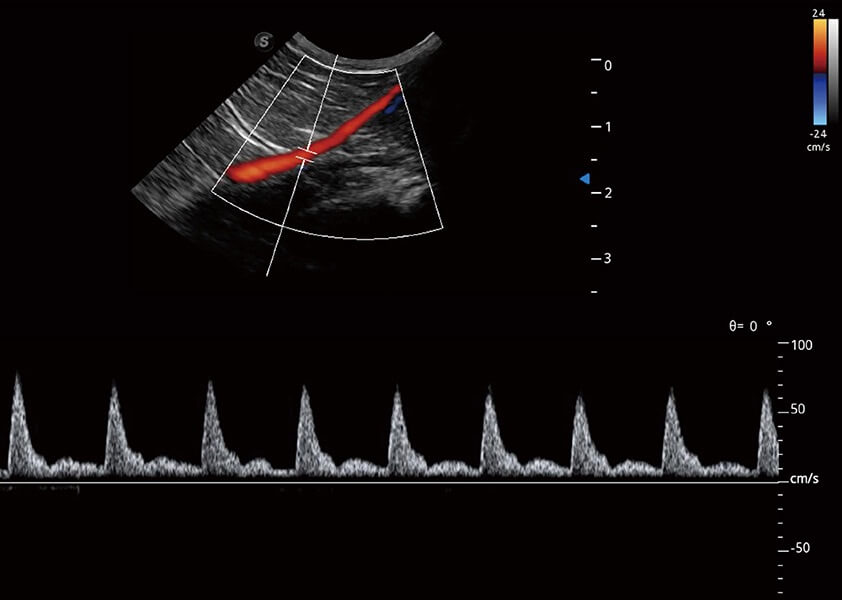

ProPet 60 作为一款高端台式动物超声设备,为动物医生的日常诊断提供了一系列贴合动物临床需求、解决临床实际问题的高级成像功能。凭借全系列高清探头,满足医生对腹部、心脏、生殖、浅表、肌骨等成像的所有需求,切实帮助您提升检查效率,提高诊断信心。

动物是人类最亲密的朋友和最值得信赖的伙伴。银河集团官网也一直致力于探索动物专用的超声影像解决方案。 全新推出的ProPet系列,是银河集团官网在动物超声影像智能化、专业化、精准化的一次跨越式革新。动物不能用言语来表述自己的不适,通过超声影像,ProPet系列搭建了动物医生与不同物种沟通的“桥梁”,为动物医生注入了“治愈之力”。